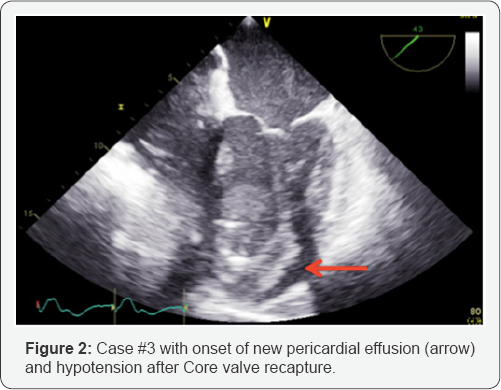

Patient #3 was a 79 year-old male with a history of prior aortic root replacement using a 27mm Medtronic Freestyle™ bioprosthesis in 2001. The patient developed severe symptomatic prosthetic AR. His STS PROM score was 3.2, but was deemed high-risk for reoperative AVR based on frailty, and porcelain aorta. The aortic annular perimeter measured 79.7mm with a derived diameter of 25.4mm by CT. Initial TAV deployment with a 29 CER, using the Super Stiff Amplatz™ wire, was too low necessitating recapture. However, this was met with endcap separation requiring a 2nd CER delivery system. Placement of the second prosthesis leads to refractory hypotension and a new pericardial effusion (Figure 2). The patient was placed on femoral cardiopulmonary bypass with attempt at redo- sternotomy, however, without success, and the patient expired.